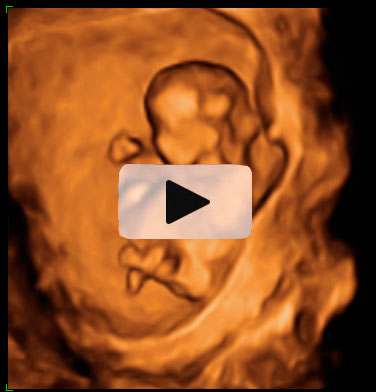

Ecografía semana 11: Bebé moviéndose en el útero

El bienestar fetal de este bebé de 11 semanas de gestación parece evidente a juzgar por su movimiento de brazos y piernas. Esta ecografía 4D ofrece el "baile" de este pequeñín, que está finalizando su primer trimestre de embarazo.

Ecografía en 4D de feto de 11 semanas moviéndose

Feto de 11 semanas de gestación con brazos y piernas en movimiento continuo dentro del útero materno. No se aprecian las extremidades con nitidez debido al "corte" de imagen que selecciona el ecografista.